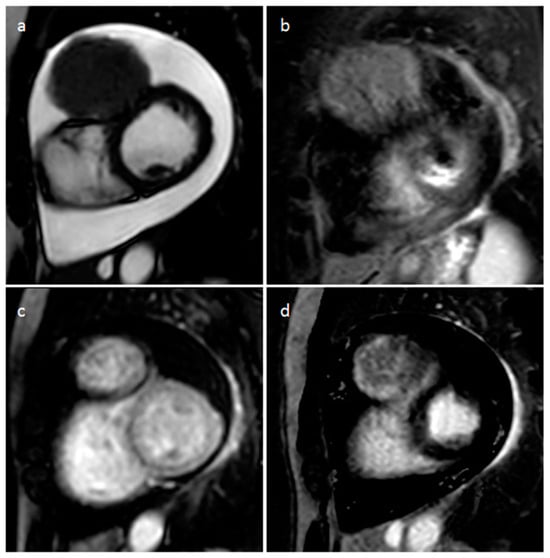

| Rhabdomyoma | Fetal life and childhood. Tuberous sclerosis | LV, IVS | Asymptomatic. Rarely flow obstruction, heart failure, arrhythmias | Intramyocardial masses, frequently multiple | Homogenous, slightly echogenic | Attenuation similar to myocardium | Iso T1w, iso-hyper T2w, no or minimal enhancement |

| Fibroma | Childhood. Gorlin Sd | LV, IVS | Asymptomatic. Rarely arrhythmias | Intramyocardial mass, solitary | Heterogeneous, echogenic, non-contractible, can mimic HCM | Soft tissue attenuation, low contrast enhancement, may show central calcification | Iso-hypo T1w, hypo T2w, no or minimal enhancement in perfusion imaging. High LGE |